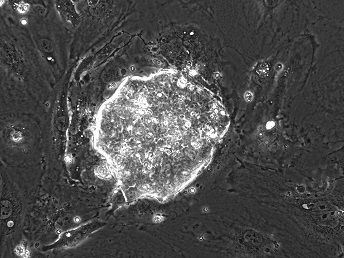

豬胚胎擴展能胚胎幹細胞(從受精第五天的German Landrace著床前胚胎中分化出的豬EPSC克隆)。